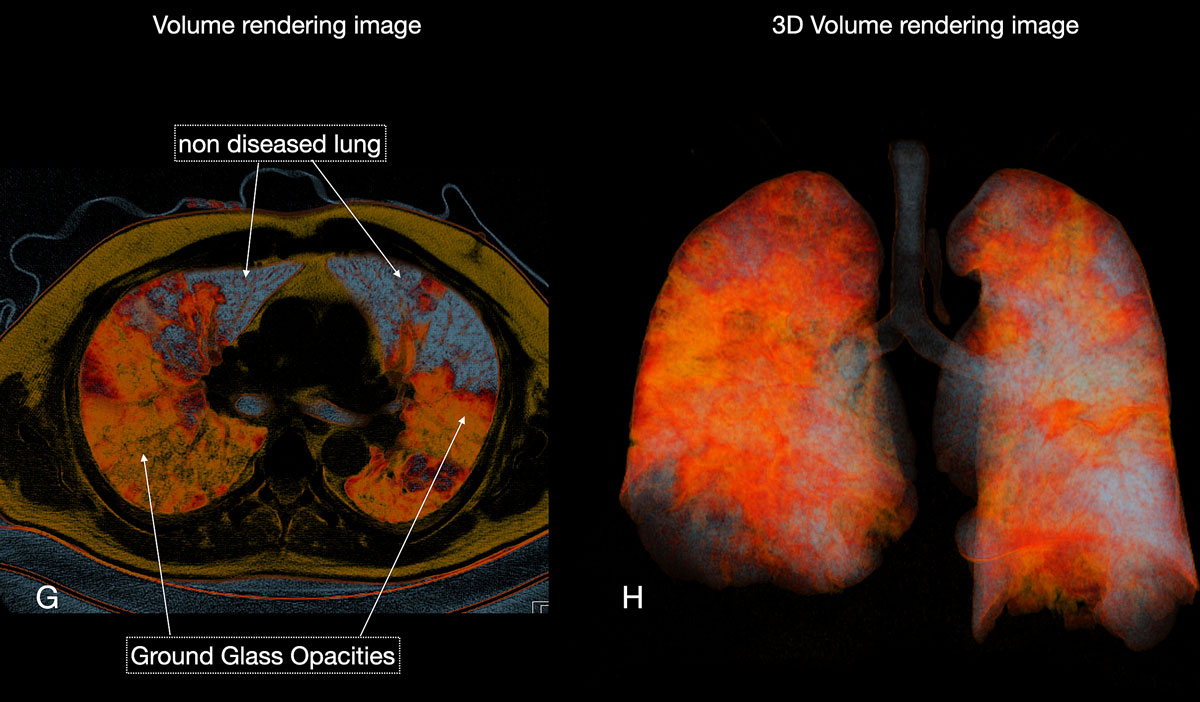

Figure 6 FG Chest CT (F) and corresponding volume rendering (G) image demonstrated the increasing extent of diseased (orange) versus non-diseased (grey-blue) lung parenchyma.

Figure 6 GH Three-dimensional volume rendering images (H) gave an overview of diseased total lung. The patient required no respiratory assistance.